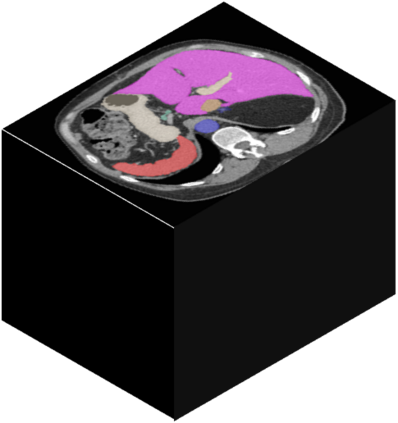

Vision transformers, with their ability to more efficiently model long-range context, have demonstrated impressive accuracy gains in several computer vision and medical image analysis tasks including segmentation. However, such methods need large labeled datasets for training, which is hard to obtain for medical image analysis. Self-supervised learning (SSL) has demonstrated success in medical image segmentation using convolutional networks. In this work, we developed a \underline{s}elf-distillation learning with \underline{m}asked \underline{i}mage modeling method to perform SSL for vision \underline{t}ransformers (SMIT) applied to 3D multi-organ segmentation from CT and MRI. Our contribution is a dense pixel-wise regression within masked patches called masked image prediction, which we combined with masked patch token distillation as pretext task to pre-train vision transformers. We show our approach is more accurate and requires fewer fine tuning datasets than other pretext tasks. Unlike prior medical image methods, which typically used image sets arising from disease sites and imaging modalities corresponding to the target tasks, we used 3,643 CT scans (602,708 images) arising from head and neck, lung, and kidney cancers as well as COVID-19 for pre-training and applied it to abdominal organs segmentation from MRI pancreatic cancer patients as well as publicly available 13 different abdominal organs segmentation from CT. Our method showed clear accuracy improvement (average DSC of 0.875 from MRI and 0.878 from CT) with reduced requirement for fine-tuning datasets over commonly used pretext tasks. Extensive comparisons against multiple current SSL methods were done. Code will be made available upon acceptance for publication.